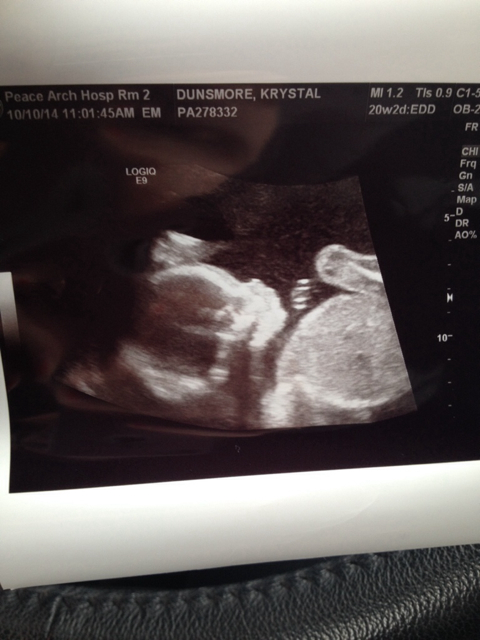

It's a babies head! Do you have a potty shot?

No sorry I thought maybe someone could try skull theory

girl guess :)